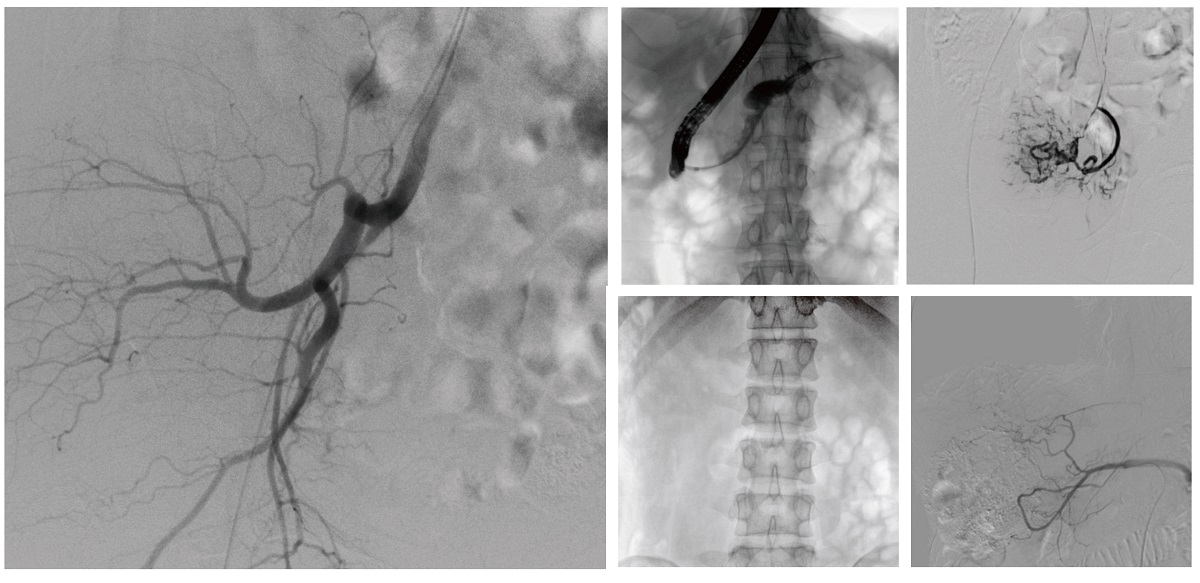

醫(yī)院引進的普愛醫(yī)療移動式平板介入中C,其高清成像能力覆蓋骨科、介入科、泌尿外科、婦產(chǎn)科等多科室,能夠滿足介入微創(chuàng)手術(shù)的多樣化需求。

設(shè)備的移動式設(shè)計,無需對現(xiàn)有手術(shù)室進行改造,適合高負荷手術(shù)量或應(yīng)急情況下的靈活部署。如在急診介入手術(shù)中,該設(shè)備能迅速響應(yīng)需求,為醫(yī)生提供實時影像支持,提升搶救效率。